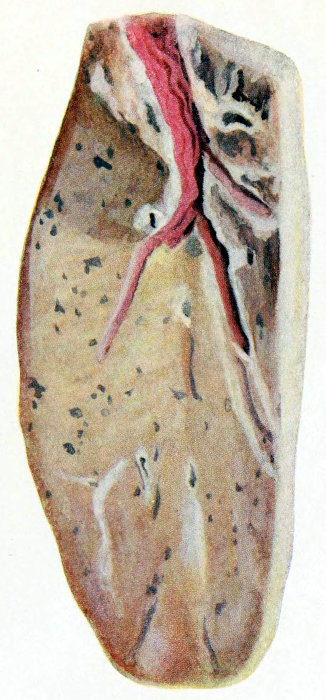

subscribe to our email newsletter to hear about new eBooks.